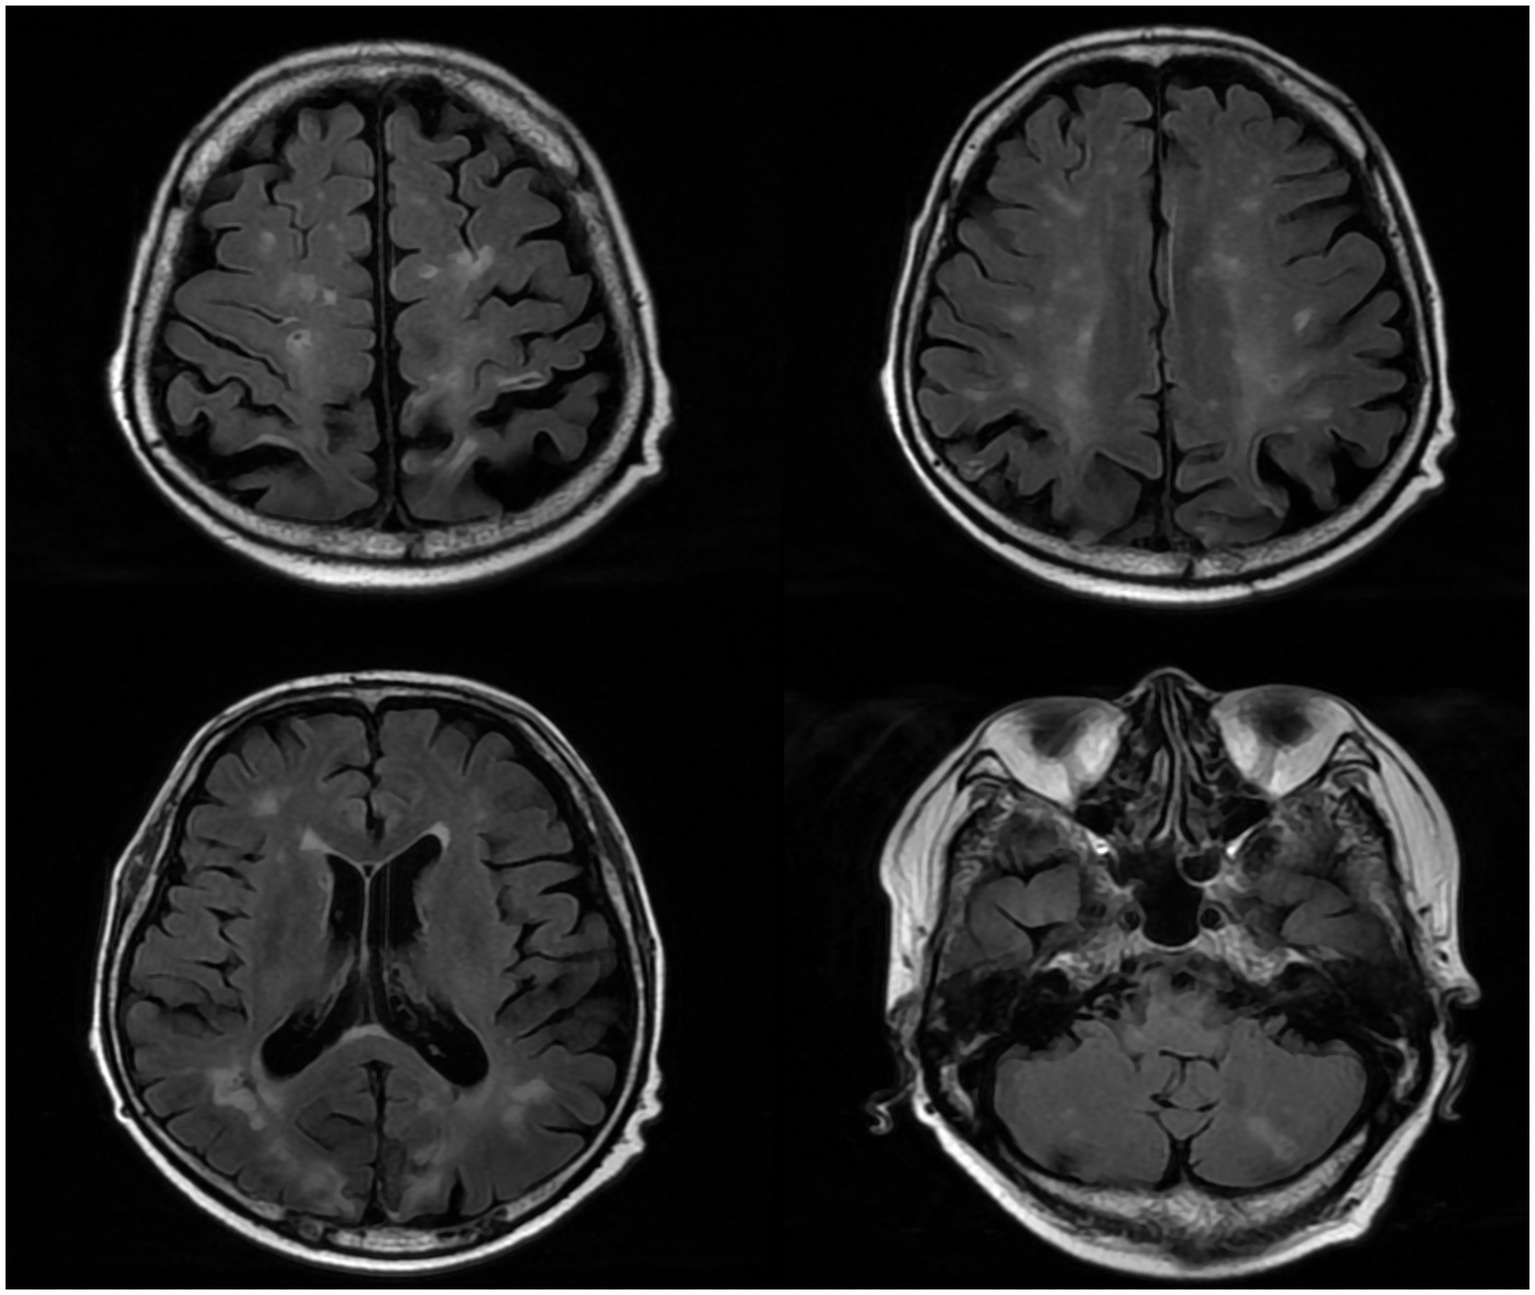

After admission, he received treatment, including rehydration, vasopressor (metaraminol bitartrate), antibiotics (imipenem-cilastatin sodium and moxifloxacin), prednisone (5 mg qd), and other support treatment. Pathogens were negative after 7 days of blood culture. On day 7 of treatment, the patient had a sudden convulsion with repetitive jerks, loss of consciousness, and eyes gazing to the right. A measure of 3 mg midazolam was injected to control symptoms, and cranial CT (Figure 3) was performed again, which revealed multiple low-density regions of both the cerebral and cerebellar hemispheres. Patent foramen ovale (PFO) was negative on transthoracic and contrast echocardiography, but it showed 0.7 cm*0.6 cm vegetation on the mitral valves (Figure 4, white arrow). Up to this point, infectious endocarditis was diagnosed.

Figure 3

Repeated cranial CT of the patient.